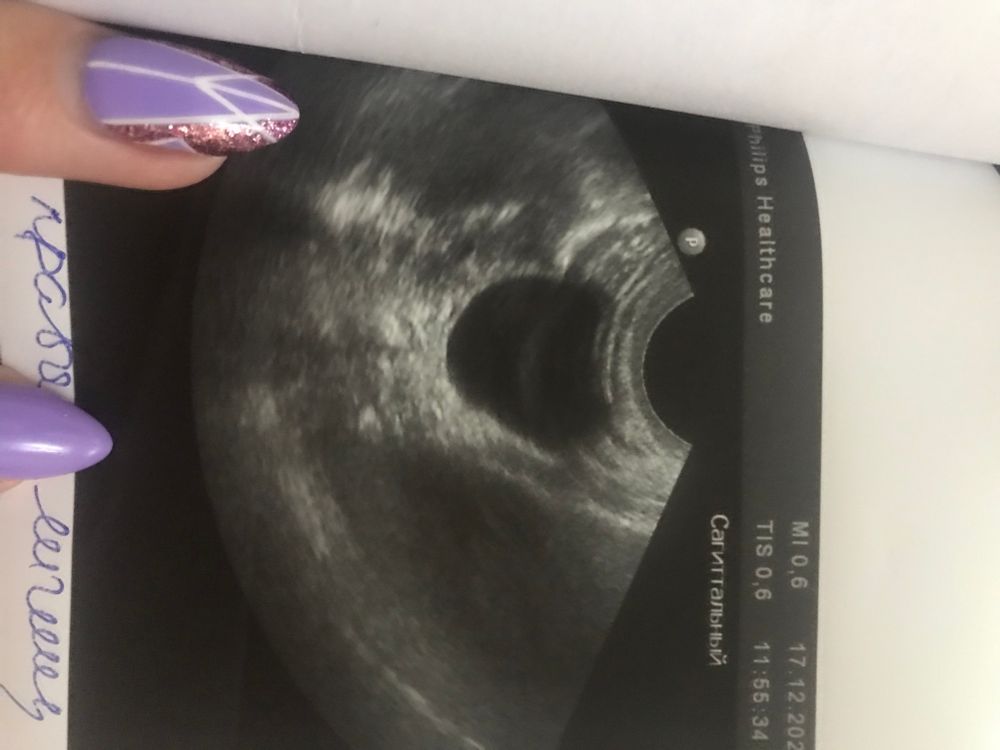

София, я так поняла, что это не киста жт…пойду к хорошему узисту 29 числа…на узи сказали, что киста 30мм а за ней типа как жт 18мм… но на узи не видно жт🤷‍♀️ Изображение

Это киста желтого тела. Это даже отчасти хорошо, значит желтое тело работает хорошо, прогестерона вырабатывается много. У меня тоже была, в 12 нед на скрининге уже не увидели, рассосалась. Не переживайте, все хорошо